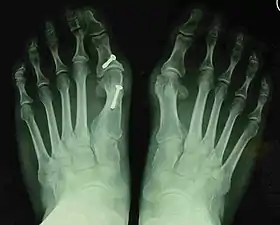

For recurrence correction after fusion procedure (Fig. 9) Metatarsus primus varus deformity and pain recurred 6 months after modified Lapidus procedure and it could also be again corrected by the syndesmosis procedure.